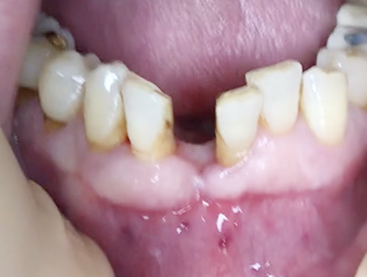

Simultaneous bone graft and implant placement